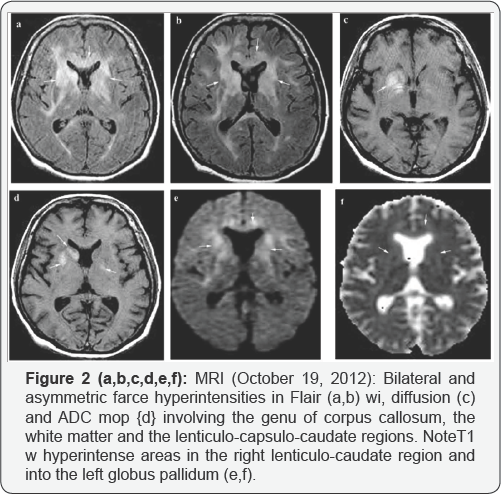

The unenhanced brain CT scan showed hypoattenuating areas involving the genu of corpum callosum and the right lenticulo-capsular region (Figure 1). Brain MRI (Figure 2) revealed multiple lesions with hyperintense signal on T2/ FLAIR sequences, isointense on T1 sequences, moderate water restriction on diffusion weighted images (DWI), some of them with moderate contrast enhancement, imprecisely delimited, localized at the level of corpus callosum, bilateral front o-insular periventricular white matter, bilateral capsulo-lenticular, right caudat nucleus, and with nodular appearance in the anterior pole of frontal lobe, left midbrain, right pons, left cerebral peduncle. The infra and supratentorial location as well as the random involvement of deep and superficial structures of gray and white matter led to the differential diagnosis among acute disseminated encephalomyelitis (ADEM), lymphoma and gliomatosis cerebri. The involvement of corpus callosum and the periventricular lesions made the diagnosis ofADEM less probable. Typical MRI findings in brain lymphomas are: homogeneous, iso- to hypointense T1 wi mass; iso- to hyperintense but often hypointense to gray matter on T2 wi with vasogenic edema; contrast enhanced T1 wi: homogeneously enhancing lesion with involvement of corpus callosum; diffusion- DWI: restricted diffusion of lesions secondary to hypercellularity, some of these MRI aspects were encountered in the presented case. The glioma hypothesis was less plausible because glioma usually shows T1-hypointense mass within white matter, with central heterogeneous signal (necrosis, intratumoural hemorrhage), variable enhancement, typically peripheral and irregular, hyperintense on T2-sequences, surrounded by vasogenic oedema and including flow voids (Figure 3). The Blood biochemistry including lactate dehydrogenase, hemoglobin, hematocrit and cell blood count were within normal range. Cerebral spinal fluid analysis showed: 7 monocytes/mm3, 0.6g/l protein (normal range =0.1-0.3g/l), 48.8mg/dl glucose (normal range 74-106mg/dl), negative bacteriological examination, negative 14-3-3 protein and absent oligoclonal bands. The bone marrow aspirate was normal, therefore a systemic lymphoma with secondary brain involvement was excluded. Enzyme- linked immunosorbent assay for detection of antibodies against human immunodeficiency virus (HIV), hepatitis B and C viruses, Epstein-Barr virus, herpes simplex virus 1 and 2, cytomegalovirus and JC virus revealed normal results. Immuno- serology showed normal immunoglobulins (IgG, IgM, IgA, IgE). After corticosteroid treatment an important clinical remission occurred, but with moderate regression of lesions on brain MRI (Figure 4 & 5). The anatomo-pathological examination of brain tissue obtained by brain stereotactic biopsy showed non Hodgkin lymphoma with large B cell. Immunohistochemical analysis revealed: lymphoma cells were positive for CD20 (diffusely distributed into the tumor) and negative for CD3, Ki67 was positive in more than 80% of tumor cells, and rare, reactive, small lymphocytes were present (Figure 3). Spinal cord MRI, contrast enhanced computed tomography of chest, abdomen and pelvis, and dilated eye examination were normal. The patient received four courses of chemotherapy combining high doses of cytarabine, methotrexate, idarubicin, dexamethasone, vincristine and ifosfamide followed by whole brain radiotherapy. The first course of chemotherapy produced an important clinical and neuroimaging remission but a new relapse occurred and the patient died 6 months later.

The typical MRI lesions of PCNSL [8] are solitary, single or multiple, homogenous, with less prominent perilesional edema, located central hemispheric, in the periventricular white matter or superficial adjacent to the meninges, with intraocular involvement in 25% of cases. On precontrast T1 weighted images, lesions are usually isointense or hypointense with strong homogenous enhancement, on T2/FLAIR appear isointense, hyperintense or hypointense, on DWI are hyperintense and on apparent diffusion coefficient (ADC) are hypointense. Lesions can disappear after corticosteroids or even spontaneously, being called "vanishing tumors". Frontal lobe location is present in 20%-43% of PCNSLs, whereas the basal ganglia are involved in 13%-20%. The corpus callosum is also frequently involved. In atypical imaging characteristics DWI, perfusion MRI and MR spectroscopy may help to differentiate CNS lymphomas from other brain lesions. DWI measures the diffusion of water molecules in biologic tissues and is considered a surrogate marker of tumor cellularity. Because PCNSL are highly cellular tumors, water diffusion is often restricted, making them appear hyperintense on DWI and hypointense on ADC maps. This characteristic is found also in: acute ischemic stroke, central necrosis of brain abscesses, the solid portion of high-grade gliomas, and some metastases. Nevertheless, PCNSL lesions have in most of cases more restricted diffusion and lower ADC values than high-grade gliomas and metastases [9]. Repeated ADC measurements may be used as biomarkers in the surveillance of therapeutic response of PCNSL [10]. Our case was particular because it showed that atypical, diffuse, imprecisely defined lesions, usually found in immunodeficient patients, especially HIV positive, can be also present in PCNSL in immunocompetent patients.